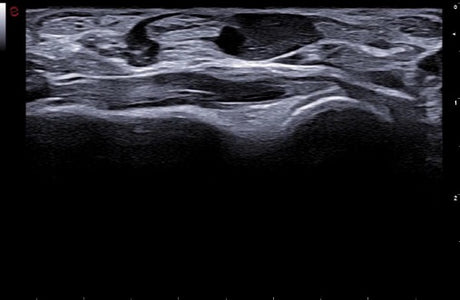

La qualité d’image est au cœur de la philosophie Esaote. Grâce à ses sondes de dernière génération et à son traitement du signal avancé, la marque permet une visualisation fine des structures anatomiques, même les plus profondes. Leurs échographes intègrent des écrans tactiles haute résolution, une interface claire et une connectivité complète, favorisant un flux de travail rapide et efficace.

Les échographes Esaote offrent une restitution d’image d’une grande précision, permettant un diagnostic fiable dans toutes les spécialités. Le traitement numérique optimise le contraste et la netteté, réduisant les artefacts et améliorant la détection des tissus pathologiques. Ces performances sont particulièrement appréciées en gynécologie, où la lisibilité des structures pelviennes ou obstétricales est déterminante.